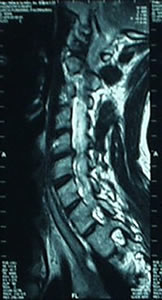

Hernia Discal cervical / Hernia Discal Lumbar

La hernia discal es la invasión del disco intervertebral hacia el canal medular, y puede producir la compresión de la médula y de los nervios sensitivo y/o motor. Es una patología frecuente en la columna cervical y lumbar y puede ser sintomática o asintomática. Los síntomas varían de acuerdo a la región; el dolor local, el dolor irradiado, las parestesias (hormigueos) en el miembro superior o inferior, los cambios repentinos en el color y sudoración de la piel, impotencia motriz, debilidad muscular y atrofia, falta de sensibilidad y contracturas son síntomas comunes a las dos regiones. Los mareos, náuseas, acufenos, migrañas y dolores punzantes en la base del cráneo son habituales en la zona cervical. Los trastornos esfinterianos, la escoliosis lumbar antalgica y el dolor ciático son propios en la hernia discal lumbar.

El tratamiento de la hernia discal en RPG consiste en lograr la convivencia entre la estructura (la columna vertebral, los ligamentos, cápsulas, los músculos) y el disco herniado, abriendo el espacio en el segmento vertebral involucrado. El abordaje será a través de: